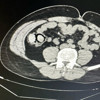

Ekiplerin çalışmaları neticesinde otobüs ile Bingöl’e gelen şüpheli yabancı uyruklu 2 şahsın iç beden muayenesinde 10 parça halinde 113 gram metamfetamin maddesi tespit edildi.